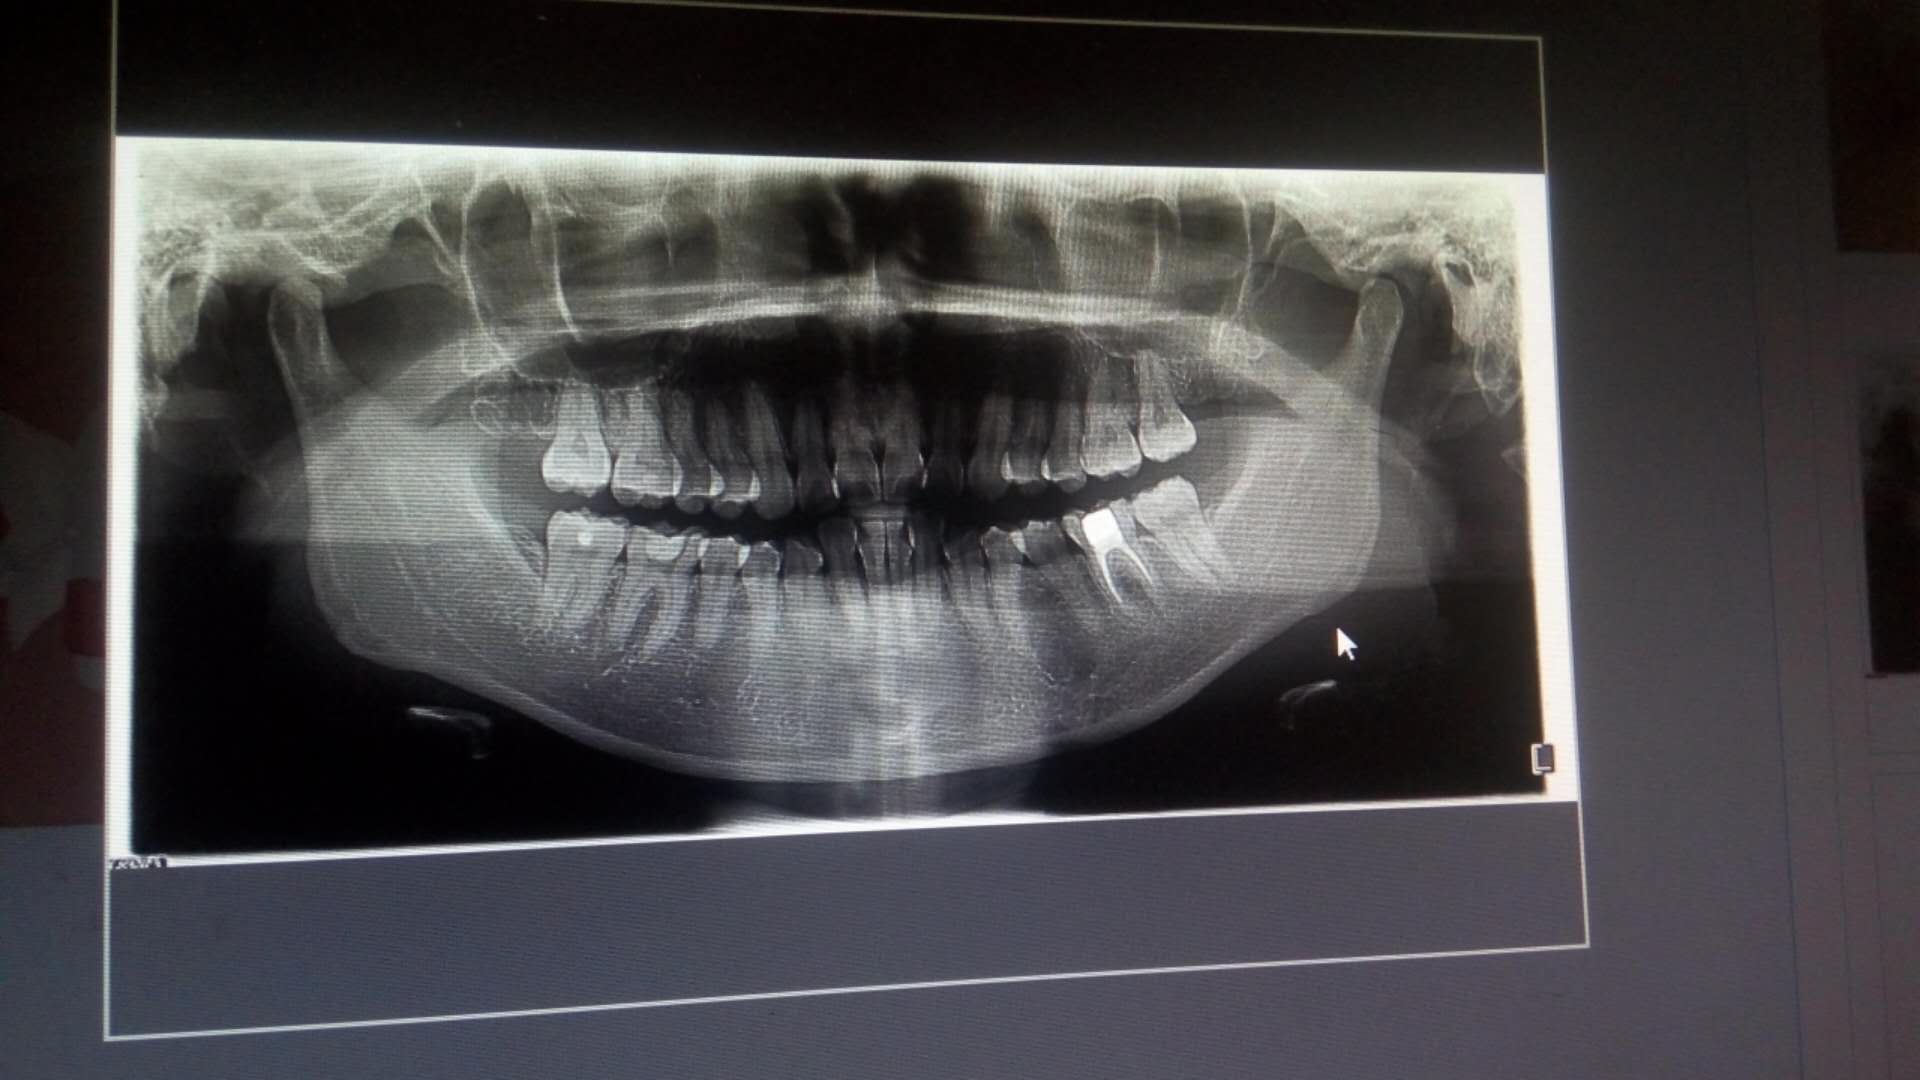

我的情况是覆盖比较深,超过了1/2,前突比较严重。顶着牙尖拍的,没敢咬牙,怕吓到人。呵呵!